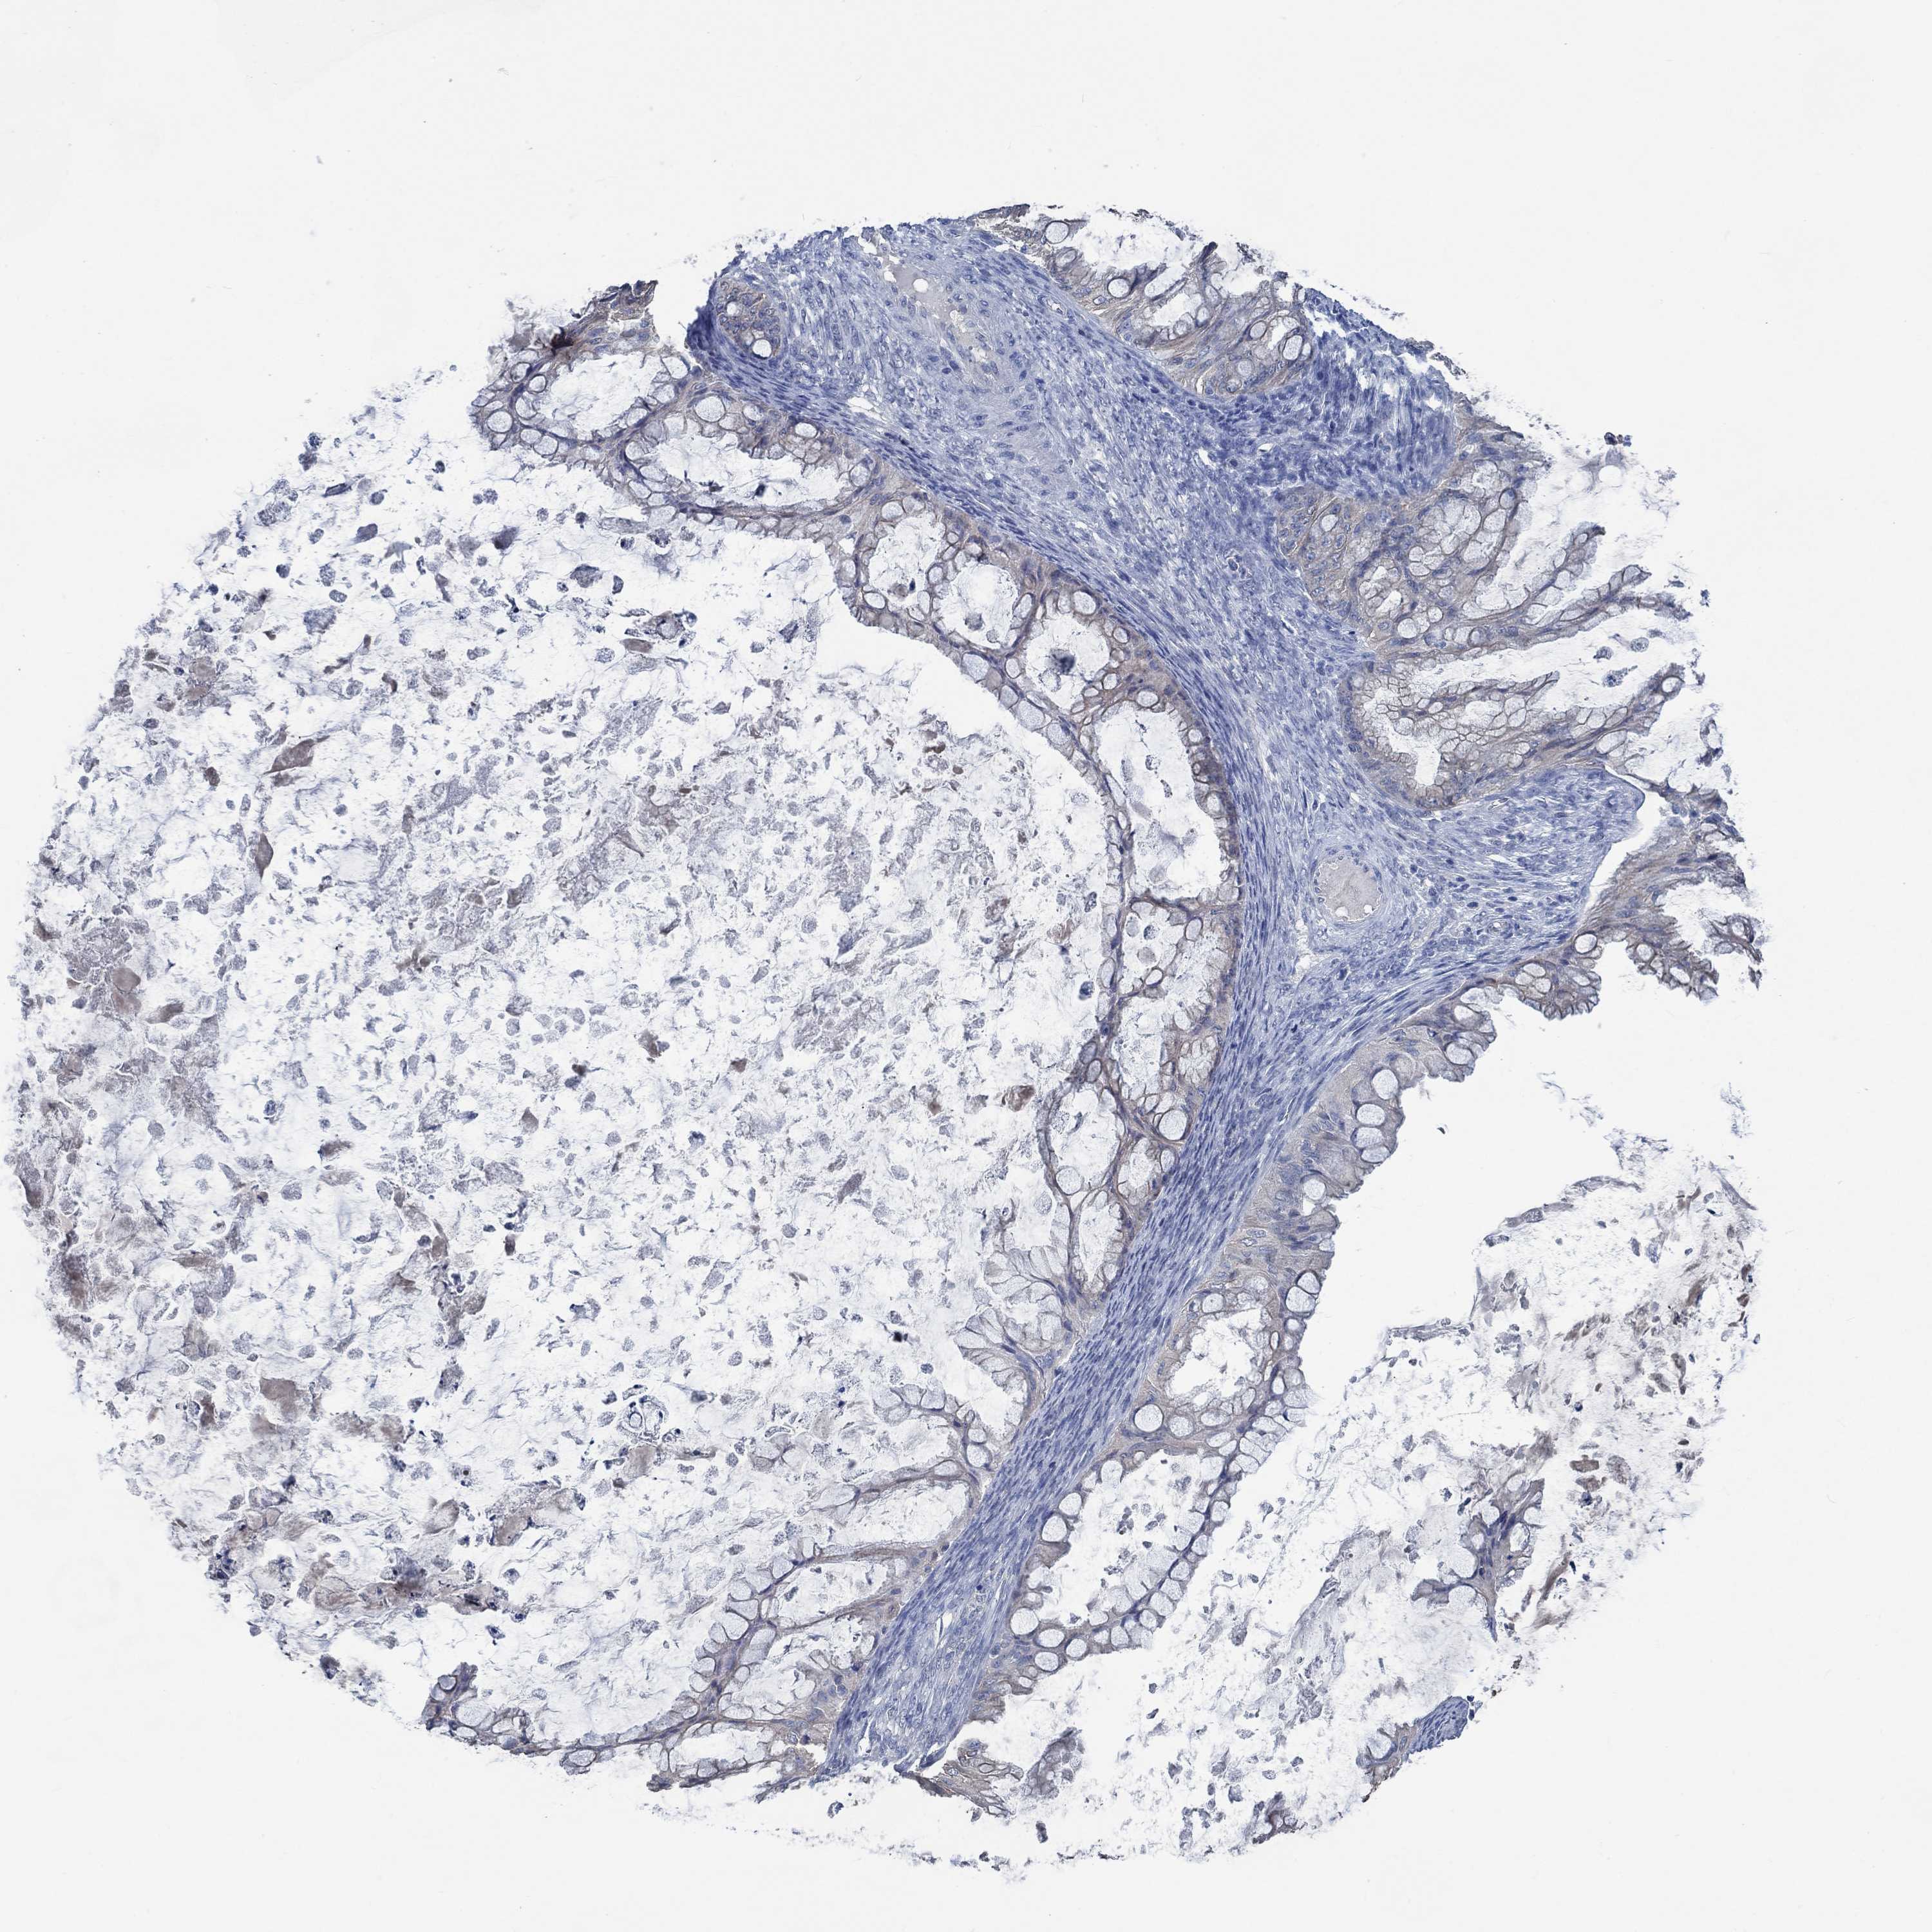

OVARIAN CANCER - Protein expressioni

A mouse-over function shows sample information and annotation data. Click on an image to view it in a full screen mode. Samples can be filtered based on level of antibody staining by selecting one or several of the following categories: high, medium, low and not detected. The assay and annotation is described here.

Note that samples used for immunohistochemistry by the Human Protein Atlas do not correspond to samples in the TCGA dataset.

Antibody stainingi

Antibody staining in the annotated cell types in the current human tissue is reported as not detected, low, medium, or high, based on conventional immunohistochemistry profiling in selected tissues. This score is based on the combination of the staining intensity and fraction of stained cells.

Each image is clickable and will lead to virtual microscopy that enables deeper exploration of all samples and also displays staining intensity scores, fraction scores and subcellular localization as well as patient and tissue information for each sample.

Antibody HPA021186

Antibody HPA065801

Staining

High

Medium

Low

Not detected

Intensity

Strong

Moderate

Weak

Negative

Quantity

>75%

75%-25%

<25%

None

Location

Nuclear

Cytoplasmic/membranous

Cytoplasmic/membranous,nuclear

Cystadenocarcinoma, serous, NOS

Cystadenocarcinoma, mucinous, NOS

Carcinoma, endometroid